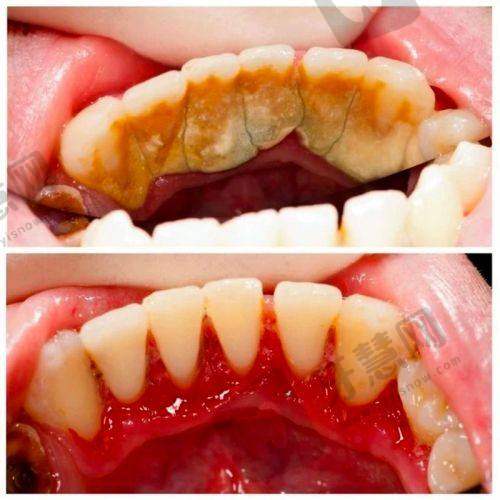

8. 超声波洁牙:89元起

19. 牙周治疗:500元起